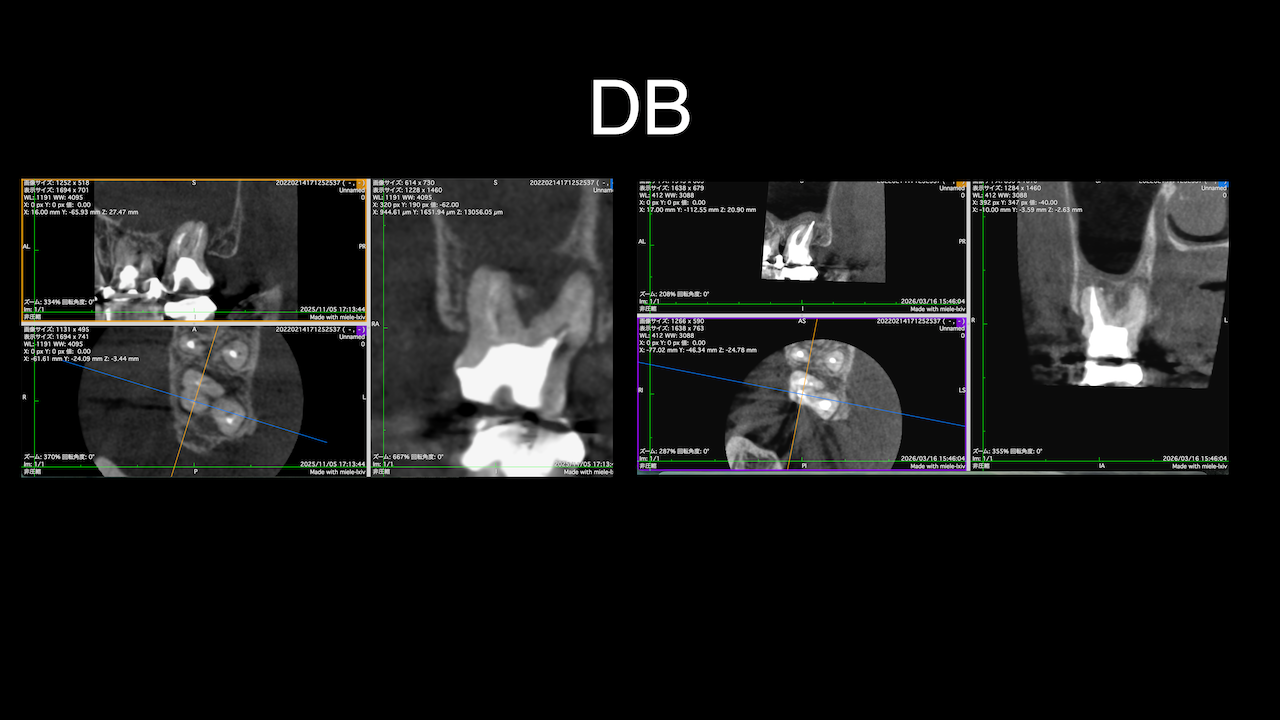

もう1ケースが以下だ。

#7がCold testに無反応である。

故に、#7,8の非外科的根管治療を行うことになった。

が、#8のメタルコアは外しにくいだろう。

CBCTでは2本とも口蓋側の皮質骨が消失している。

という絶望的な状況である。

が、

術前にその予後を患者さんに説明し、

治療へ移行した。

その結果、

ここから4ヶ月が経過すると…

臨床症状も皮質骨も大きく治癒している。

1年後の予後が気になるところであるが、すごくよくマネージメントできているだろう。